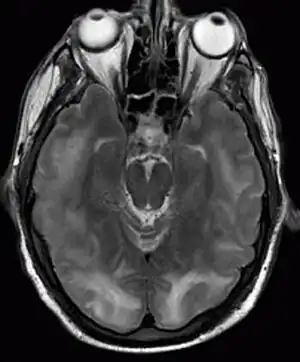

a) Cortical hyperintensity in posterior parieto-occipital lobe b)10 days after symptom onset shows resolution

There is no direct treatment for PRES, other than removing or treating any underlying cause. For instance, immunosuppressive medication may need to be withheld.[1][4] 40% of all people with PRES are unwell enough to require intensive care unit admission for close observation and treatment of complications.[2] Those with seizures are administered anticonvulsants.[1]